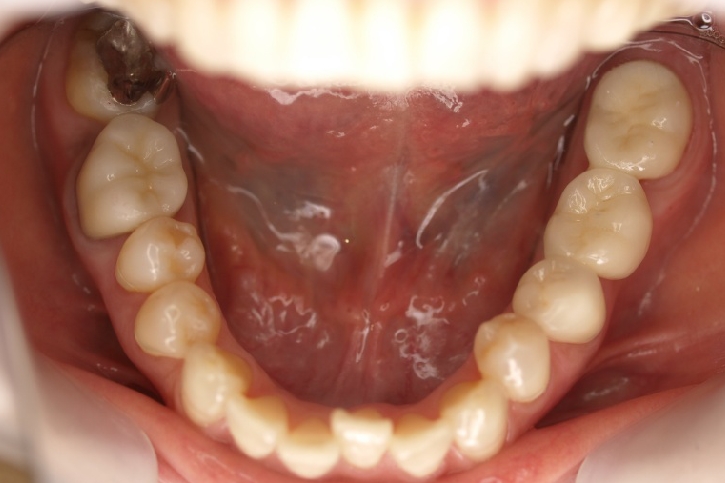

ゴールド修復

担当歯科医師:丸林浩太郎

2013年2月5日千葉市中央区 T.S様 左右6番ゴールドインレー・クラウン修復